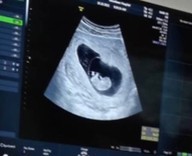

10 w ตัวใหญ่เหมือน 11 4.3 เซน